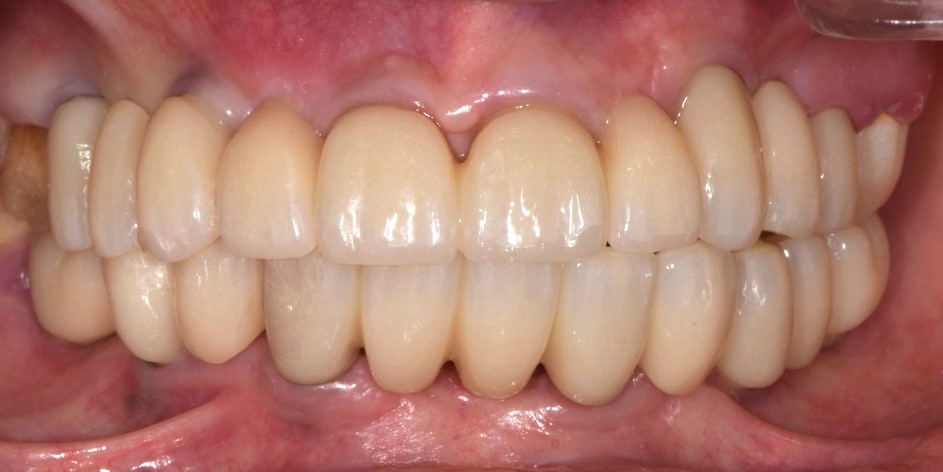

Protesi finale

Fig. 6(a)

Protesi finale 2

Fig. 6(b) Protesi finale.

I restauri si adattavano perfettamente, poiché il design dell'abutment iPhysio® aveva modellato i tessuti molli in modo così predicibile da poter essere riprodotto digitalmente sul profilo di emergenza della protesi finale (Fig. 7 a,b,c,d,e,f).